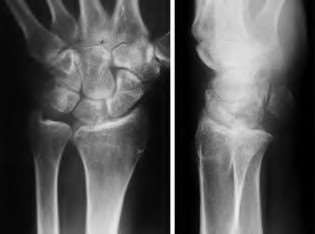

A 20-year-old park ranger trips and falls onto his right wrist with the wrist in extension and pronation. The local urgent care orders both radiographs and a CT, which you review and determine to be normal. The patient complains of ulnar-sided wrist pain. On exam, his tenderness is localized to the fovea. Ulnar deviation also causes him pain. There is no snapping sensation with wrist supination, flexion, and ulnar deviation. He otherwise has 5/5 strength to his first dorsal interosseous muscle with 4mm static two-point discrimination on the ulnar side of the 4th digit. Which of the following injuries is most likely responsible for his symptoms and exam?